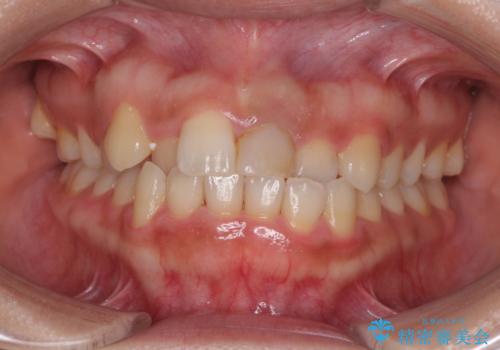

歯並びのがたつきを直したい ワイヤーは嫌 抜きたくない